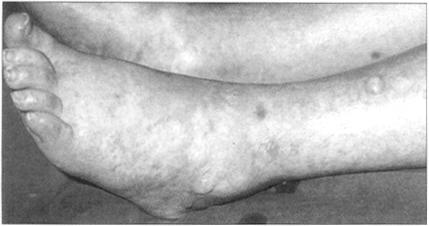

(10)胸部和踝部的检查 在对被检查者进行心血管系统检查后,还应让受检者取前倾坐位,注意听诊肺底有无水泡音或胸腔积液。同时还应检查踝部,看其有无水肿,检查方法是用手指用力按压胫前,松手后看有无指压迹存在。

外周性水肿(图36)是右心衰竭的主要表现,这一点可以通过按压胫前皮肤得以证实,如手指移开后有压迹残留,则存在外周性水肿。

图36 周围水肿伴水泡